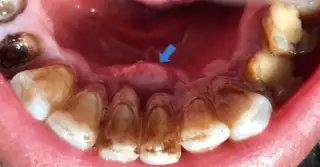

Gingivitis can be attributed to poor oral hygiene and it can be avoided by brushing your teeth at least twice daily along with flossing. Gingivitis happens due to the formation of plaque on your teeth that turns into tartar where bacteria can flourish. Once plaque has formed into tartar, it becomes difficult to remove the plaque. If not removed early, the bacteria start causing irritation to the gingiva which results in inflammation of the gums.

The symptoms of gingivitis include gum bleeding while flossing or brushing, receding gums, swollen gums, tender gums, dark red gums, and bad breath.

When dental plaque gets accumulated in large quantities, it results in chronic periodontitis. The most prevalent symptoms are bad breath, bleeding gums, pus between the teeth and gums, gums that are puffy or swollen, and bright red or purple which feels tender when they are touched.